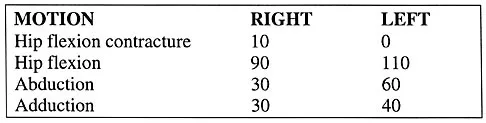

The parents of a previously healthy 3-year-old child report that she refused to walk on awakening. Examination later in the day reveals that the patient can walk but with a noticeable limp. She has a temperature of 99.5 degrees F (37.5 degrees C). Range of motion measurements are shown in Figure 50. An AP pelvis radiograph is normal. Laboratory studies show a WBC count of 9,000/mm3 and an erythrocyte sedimentation rate of 10 mm/h. Management should consist of